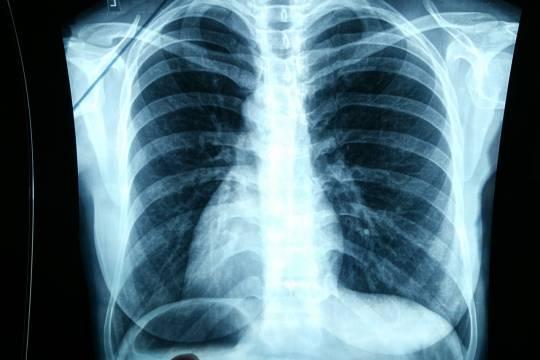

В Мариинско-Посадском районе Чувашии больного туберкулезом будут лечить принудительно

Одного из жителей Мариинско-Посадского муниципального округа Чувашии, который болен заразной формой туберкулеза, госпитализировали в принудительной форме в специальное медучреждение для проведения необходимого лечения. Районная прокуратура проверила исполнение закона об охране здоровья, в данном случае, по предупреждению распространения туберкулеза. В ходе проверки был установлен факт уклонения гражданином от лечения заразной формы туберкулеза.

Выяснилось, что один из местных жителей, страдающий заразной формой туберкулеза, проходил лечение в республиканской туберкулезной больнице, но весь курс больной не прошел и сбежал из больницы раньше срока. К тому же, он регулярно нарушал санитарно-эпидемиологический режим. А с сентября 2022 года заразный вообще избегал обследования и отказывался от лечения.

Таким образом, своими действиями больной создавал угрозу окружающим, нарушал их права на охрану здоровья и санитарно-эпидемиологическую среду. По закону (ст.10 ФЗ «О предупреждении распространения туберкулеза в Российской Федерации») такие больные по решению суда должны быть госпитализированы в специализированные медучреждения для принудительного обследования с лечением, сообщает пресс-служба прокуратуры ЧР. В результате для защиты прав и законных интересов местных жителей, живущих на поднадзорной территории, окружной прокурор направил в Мариинско-Посадский районный суд административное исковое заявление о принудительном лечении правонарушителя. Направленное прокурором соответствующее заявление районный суд рассмотрел и принял решение о незамедлительном исполнении запрашиваемых прокуратурой мер.